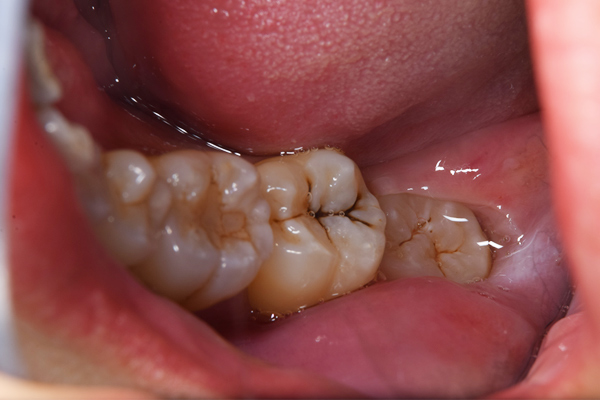

上顎はしっかり親知らずがはえています。下顎は右(青)はしっかりはえていますが、虫歯になっています。下顎の左(赤)は斜めにはえています。またこちらも虫歯になっています。

親知らずは、のどに近いですし、頬っぺたもありますので、なかなか磨くのが難しいですね。そのため、虫歯になりやすい傾向にあります。また、プラーク(歯垢)除去がしずらいため、親知らずの周りの歯茎が腫れたり、出血しやすくなります。

こちらは、下顎の親知らずが半埋伏で斜めにはえています。また、前の歯との間に虫歯をつくってしまっていたり、前の歯の根の先端の方まで骨が溶けてしまっています(智歯周囲炎)。

このように他の残さないといけない歯に悪影響を与えている親知らずに関してはなるべく早めに抜いたほうがよいです。